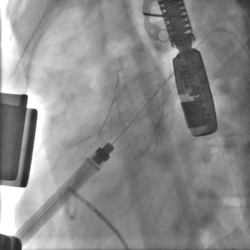

肺动脉瓣释放DSA

肺动脉瓣植入后DSA